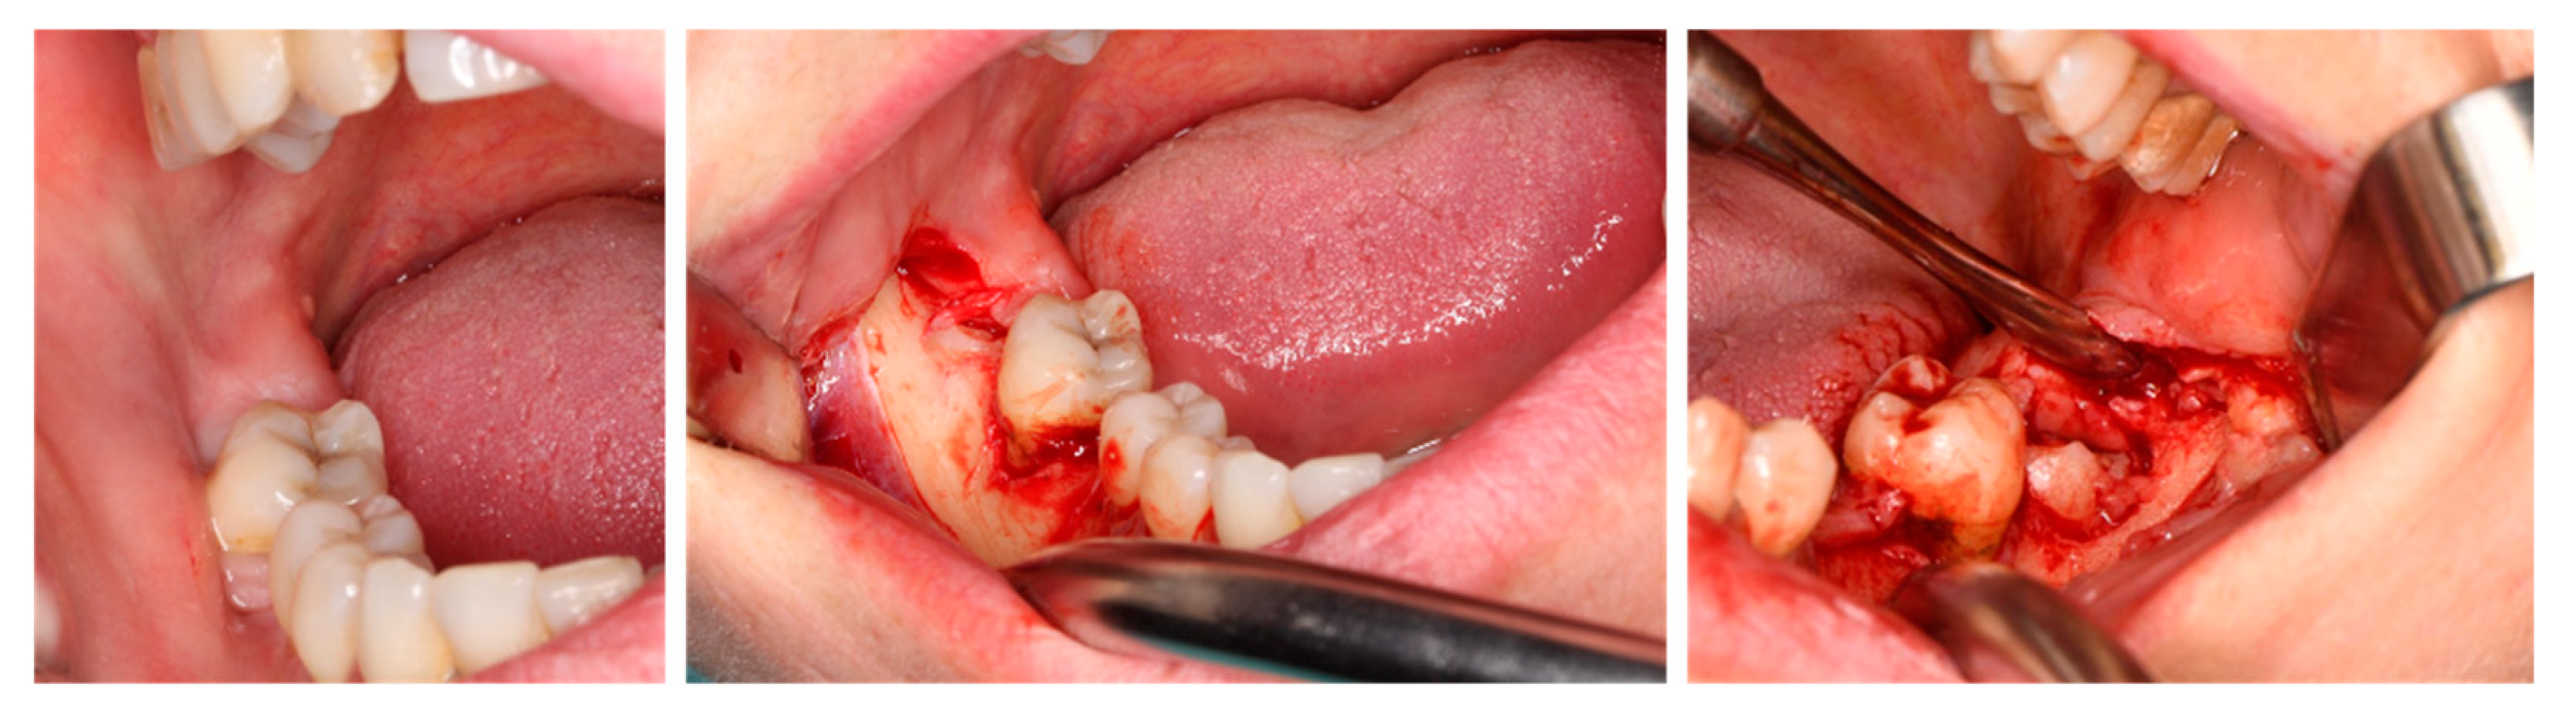

1. Introduction

2. Materials and Methods

2.4. Surgical Procedure